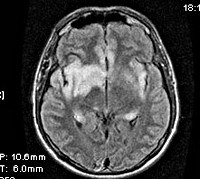

Подтвердить наличие энцефалита, определить распространенность и преимущественную локализацию воспалительных изменений позволяют КТ и МРТ головного мозга. КТ головного мозга визуализирует зону поражения церебральных тканей как имеющую пониженную плотность, МРТ в Т1-режиме - как гипоинтенсивную, МРТ в Т2-режиме - как гиперинтенсивную. МРТ обладает большей чувствительностью, что особенно важно на начальных стадиях заболевания.